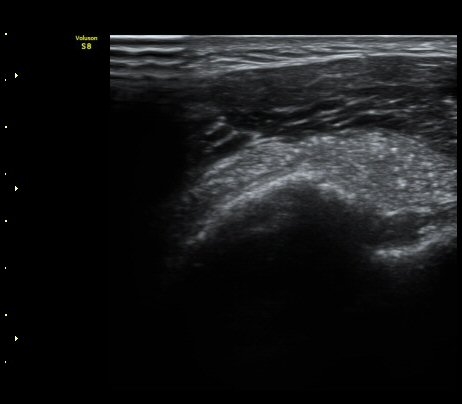

ÃÊÀ½ÆÄ °Ë»ç

À̵ιڱ٠Ⱦ´Ü¸é°Ë»ç¿¡¼­ Á¡¾×³¶³» °í¿¡ÄÚ ¼®È¸È­ À½¿µµéÀÌ °üÂûµÊ(±×¸² 1, 2, 5)

¿ÜȸÀüÀÇ Á¦ÇÑÀ¸·Î °ß°©ÇϱٰÇÀÌ ¼öÆòÀ¸·Î °üÂûµÇÁö ¸øÇϰí À̵ιڱ٠ǥÃþ¿¡

¼®È¸È­ À½¿µÀÌ °üÂûµÊ(±×¸² 3)

À̵ιڱ٠Á¾´Ü¸é°Ë»ç¿¡¼­µµ Á¡¾×³¶³» ¼®È­È­ À½¿µÀÌ °üÂûµÊ(±×¸² 4).

ÁÖ»ç ÈíÀΰú Á¡¾×³¶³» ÁÖ»çÄ¡·á(÷ºÎ ÆÄÀÏ) 1ÀÏ ÈÄ ½ÃÇàÇÑ °Ë»ç¿¡¼­ Á¡¾×³¶ÀÇ ºÎÁ¾ ¹× ¼®È¸ÀÇ

Á¦°Å°¡ °üÂû µÊ(±×¸² 6, 7).